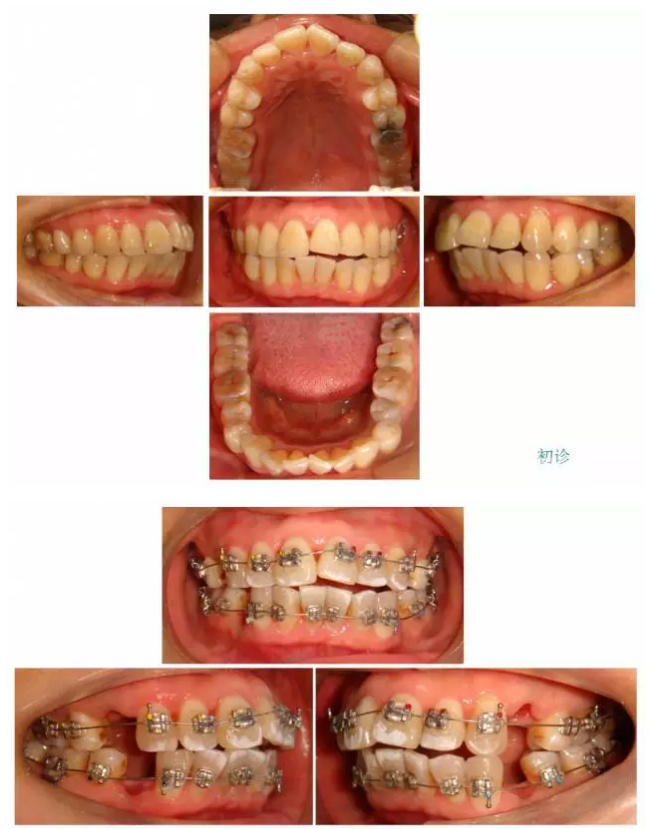

【原創(chuàng)博客】這樣的代償矯治大家滿(mǎn)意嗎?(重度骨性二類(lèi))——侯志明

轉(zhuǎn):侯志明 愛(ài)齒-KQ88口腔醫(yī)學(xué)